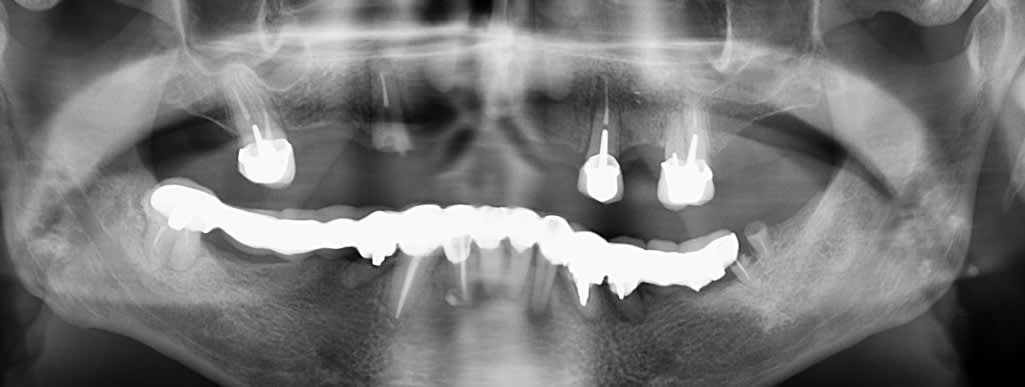

Voila voila...

Sinon la pano est pas très jolie mais pas évident de faire mordre sur la petite tige ici :P